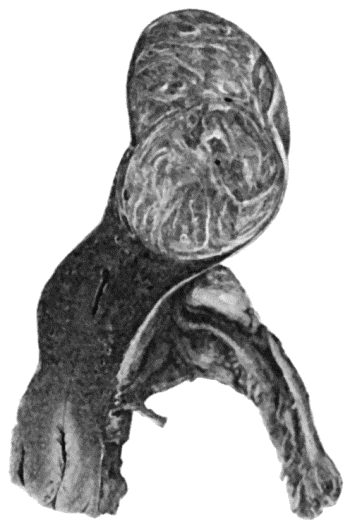

89.Elephantiasis Neuromatosa in a woman æt. 28 359